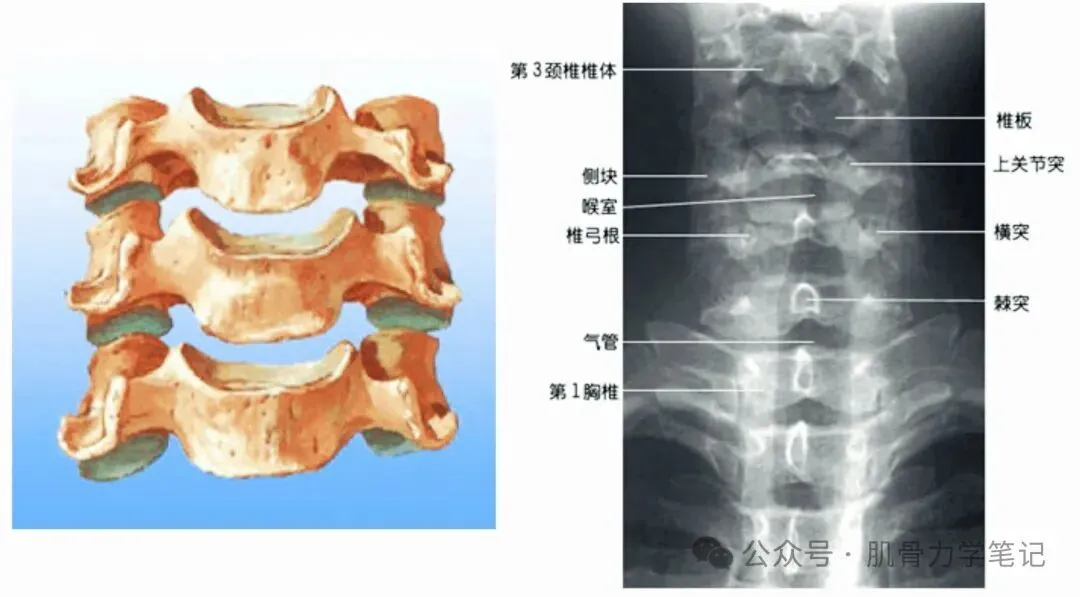

二、颈椎X影像解剖观察

(一)正位片观察要点